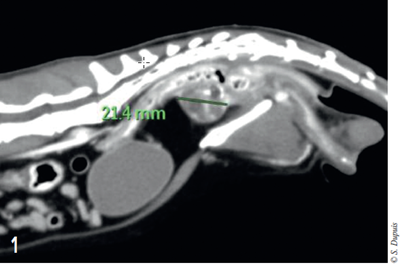

Néanmoins cet examen ne permet pas d’explorer la filière pelvienne dans son entièreté. Un examen d’imagerie complémentaire type scanner de l’abdomen est donc réalisé. L’examen de la filière pelvienne montre une masse sphérique hétérogène de 2,1 cm de diamètre, centrée sur l’urètre (figure 1).

Photo 1 – Coupe sagittale tomodensitométrique de l’abdomen. La mesure montre le diamètre de la masse

Cette masse déplace le côlon dorsalement à gauche. Elle se trouve à 18 mm de la vessie dorsalement à la symphyse pubienne (figure 2).